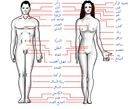

الرأس: جمجمة - جبهة – عين – أذن – أنف – فم – لسان – أسنان – فك – فك سفلي – وجه – خد – ذقن

الرقبة: حلق - حنجرة – تفاحة آدم

جذع: كتف – عمود فقري – ثدي – حلمة – صدر – قفص صدري – بطن – سرة

أطراف: ذراع – مرفق – ساعد – رسغ – يد – اصبع (إبهام - سبابة - وسطى - بنصر - خنصر) – رجل – حـِجر Lap – فخذ – ركبة – رَبـْلة الساق Calf muscle – كعب – كاحل – قدم – اصبع قدم (إبهام القدم Hallux)